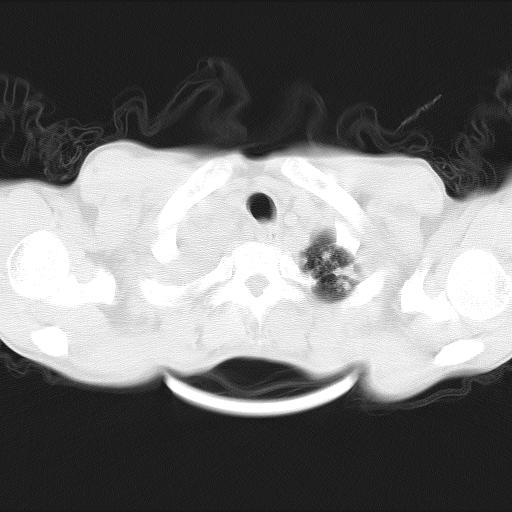

男性,44岁,结核病史多年。现胸闷气短,咳嗽,偶咳血。

1)两肺继发性肺结核伴空洞形成,左肺多发性结核球。2)右侧大量胸腔积液伴右肺部分膨胀不全。3)纵隔淋巴结肿大。

1,双肺多发结节 并空洞影改变, 左侧胸腔积液并部分包裹, 结合原病史首先考虑结核. 但也不除外其它.

2,左侧有一根肋骨陈旧性骨折? 建议追查 .

吉大一院胸水抽检结果:结核性胸水